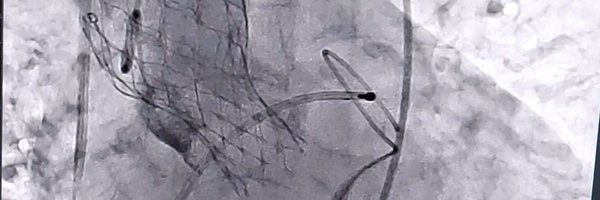

4th nicvd CTO workshop. 9 challenging cases. Retrogrades, ADRs and a lot more. @nicvdintvcard @nicvd_karachi @AllanaSalman @rzakir12 @ACCinTouch @SCAI @CtoEuro @md_SsAhmad @LAzzaliniMD @AKUGlobal @AkuCardiology @AnkurSethi2021 @esbrilakis @jas_sheerazi @escardio @shaoliang_chen

4

2

43